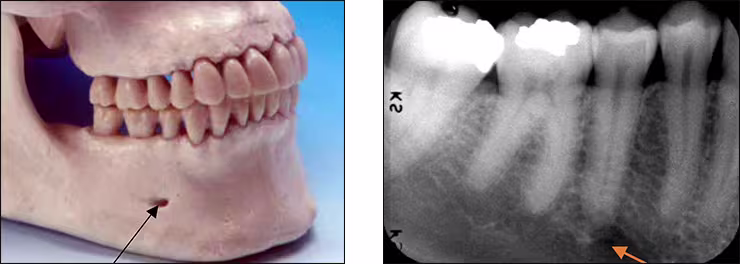

Mental foramen – The mental foramen, the primary landmark of this area, is a circular radiolucent structure located below the roots of the mandibular premolar teeth. This structure is the opening for passage of the mental nerve and vessels and can be observed on mandibular premolar and the lateral aspect of canine periapical images. This bilateral radiolucency can be misinterpreted as a periapical lesion. However, it is easily differentiated upon closer examination of the tooth and its supporting structures.

Mandibular canal – The mandibular canal is the pathway in bone where the inferior alveolar nerve and blood vessels course through the mandible. The canal extends from the mandibular foramen within the ramus anteriorly to the mental foramen. This tubular bilateral radiolucency often demonstrates fine radiopaque boundaries. The mandibular canal is recorded on mandibular premolar and molar periapical images. It is also referred to as the inferior alveolar nerve canal. The mandibular foramen is not recorded on mandibular periapical images.